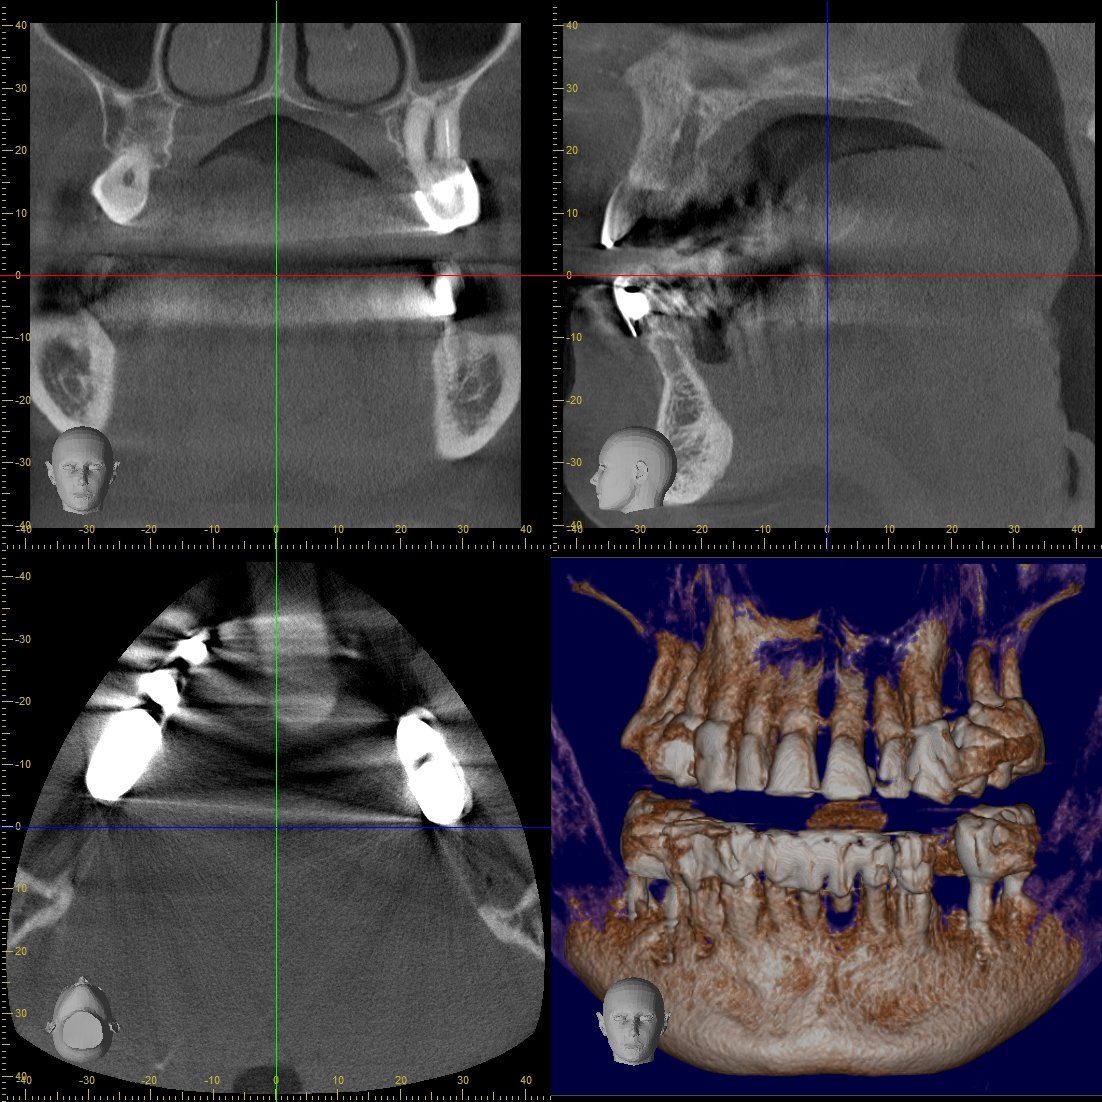

Digitales 3D-Röntgen (DVT)

Präzise 3D-Diagnostik für Implantate und komplexe Behandlungen

Unser modernes DVT-Gerät ermöglicht dreidimensionale Aufnahmen des Kiefers mit

minimaler Strahlenbelastung. Die präzisen 3D-Bilder sind Grundlage für

implantologische Behandlungen, Wurzelkanaltherapien und die Planung komplexer

zahnärztlicher Eingriffe.

Geringste Strahlenbelastung im Vergleich zu herkömmlichen Röntgengeräten

Hochpräzise 3D-Bilder für exakte Behandlungsplanung

Schnelle Aufnahme in nur wenigen Sekunden

Komfortable und angstfreie Untersuchung für Patienten